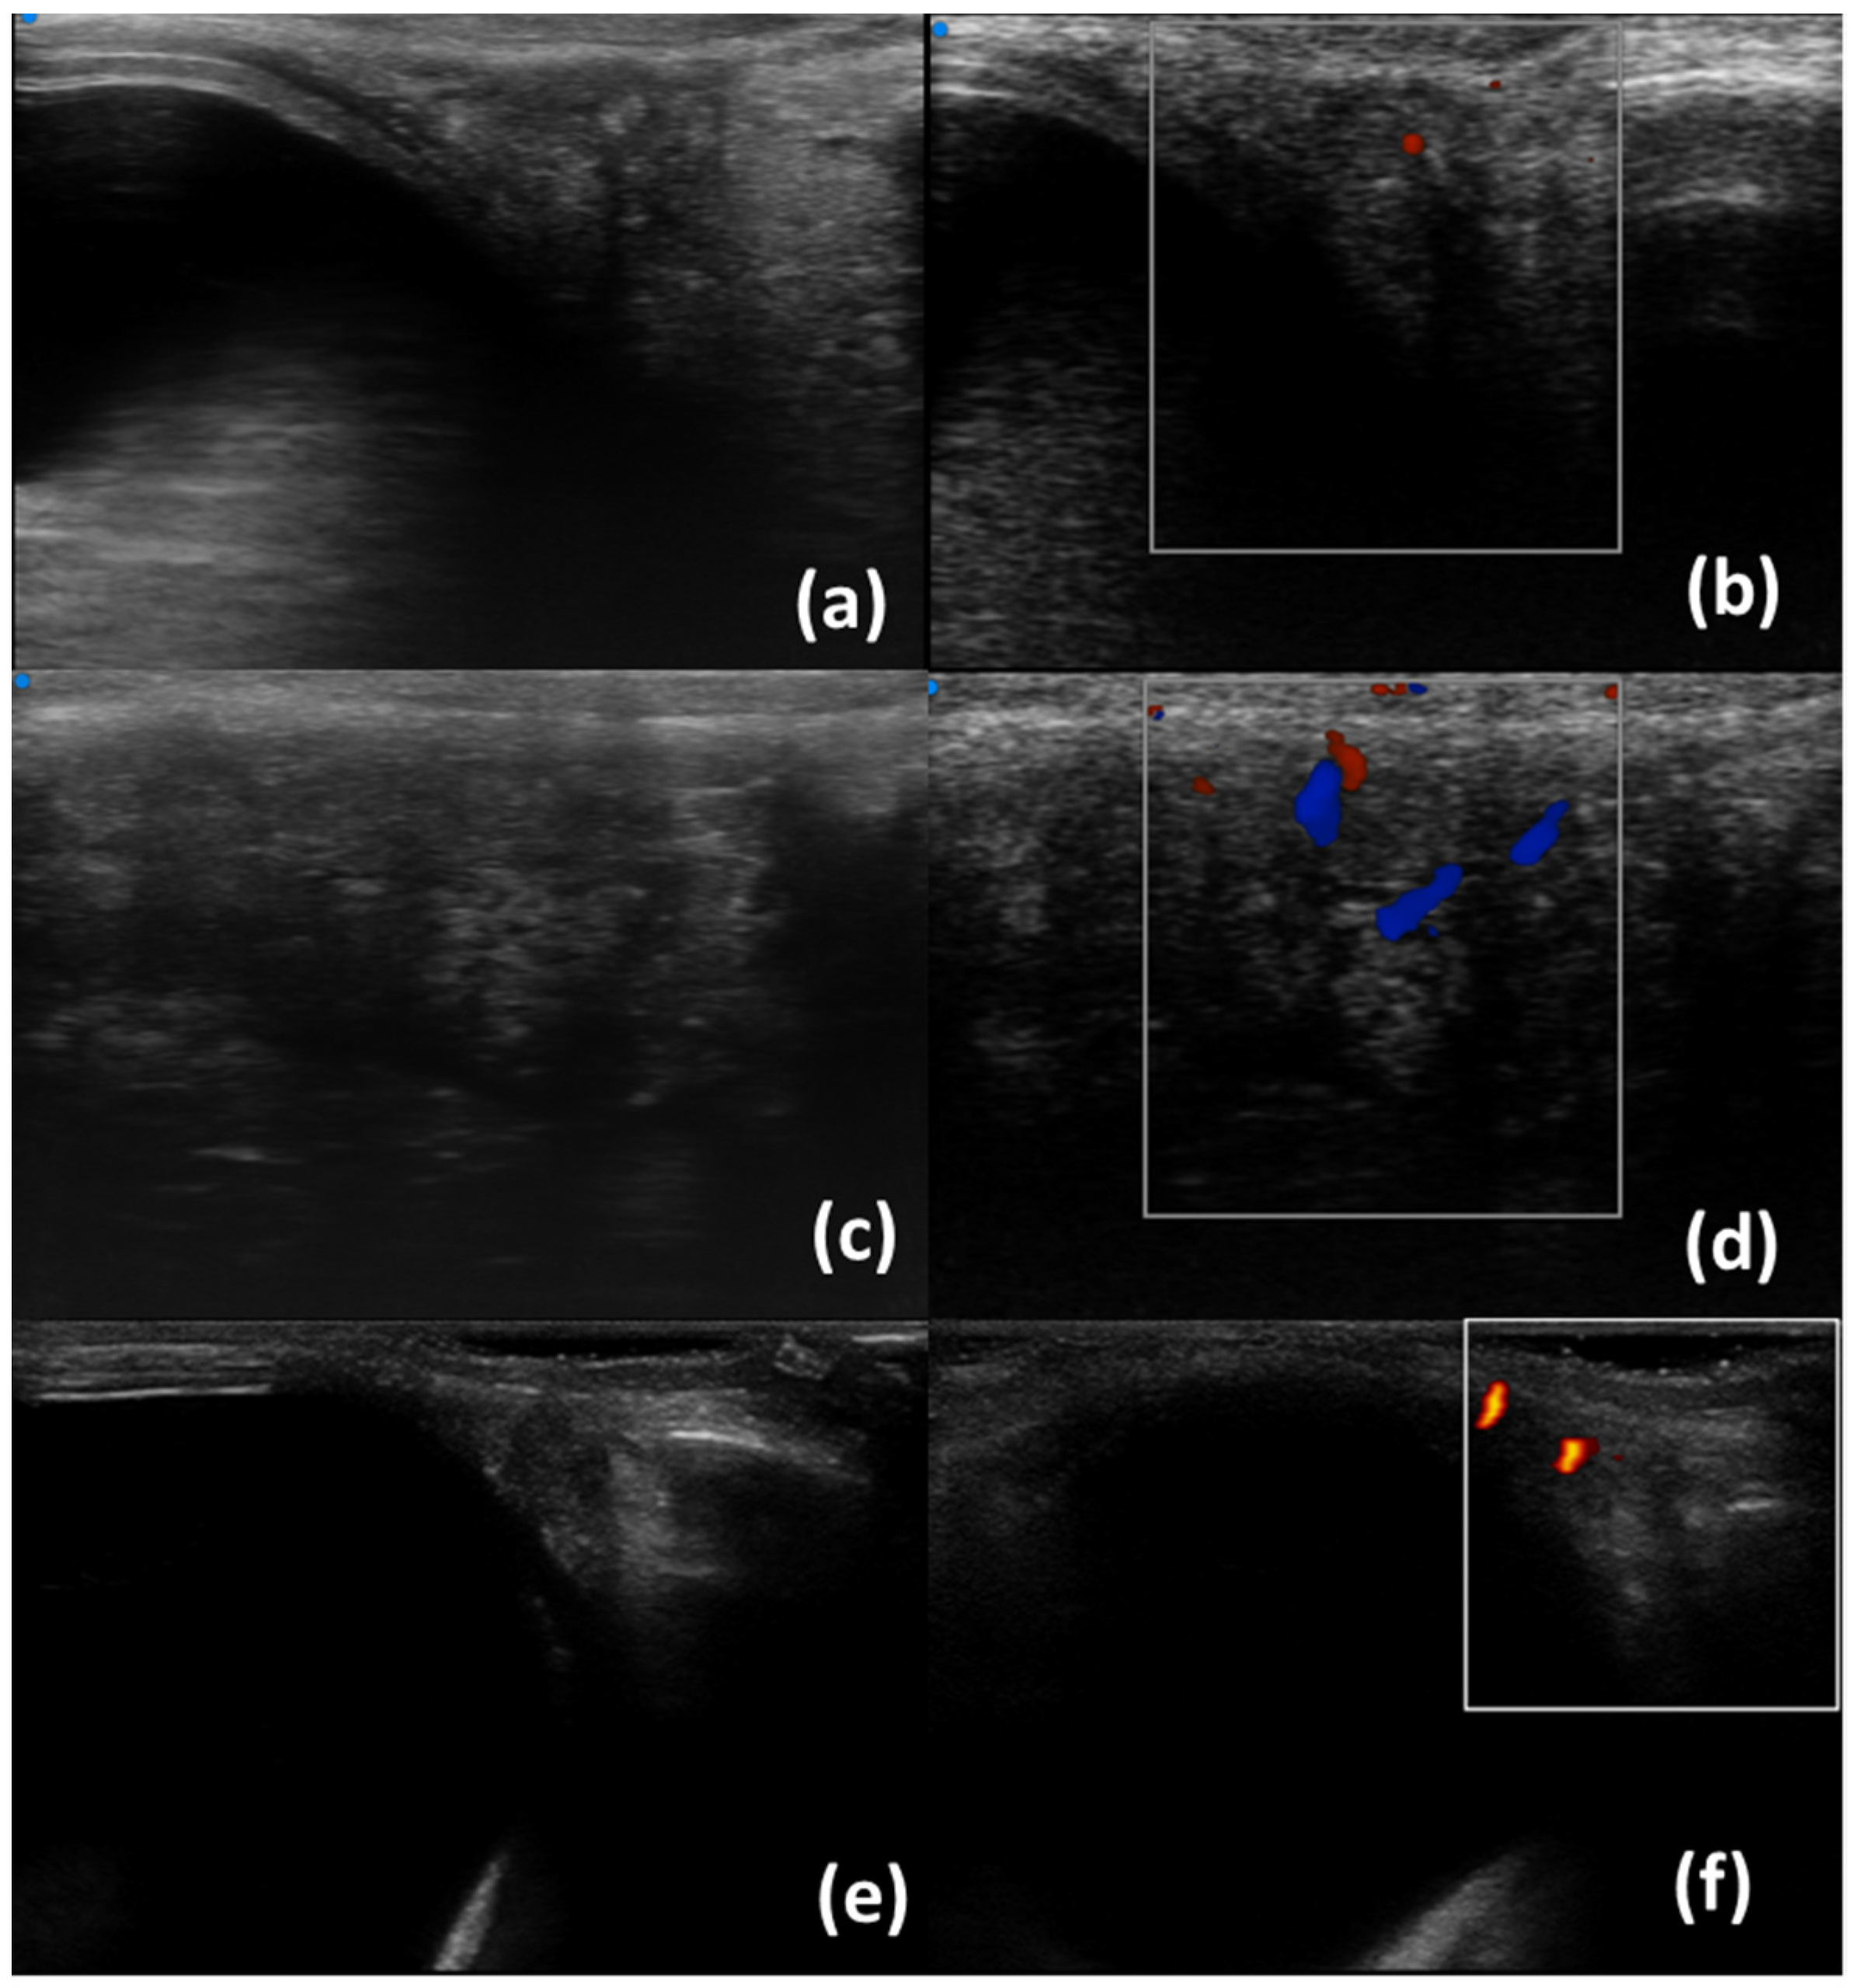

- Aringhieri, G.; Izzetti, R.; Vitali, S.; Ferro, F.; Gabriele, M.; Baldini, C.; Caramella, D. Ultra-high frequency ultrasound (UHFUS) applications in Sjogren syndrome: Narrative review and current concepts. Gland. Surg. 2020, 9, 2248–2259. [Google Scholar] [CrossRef] [PubMed]

- Ferro, F.; Izzetti, R.; Vitali, S.; Aringhieri, G.; Fonzetti, S.; Donati, V.; Dini, V.; Mosca, M.; Gabriele, M.; Caramella, D.; et al. Ultra-high frequency ultrasonography of labial glands is a highly sensitive tool for the diagnosis of Sjögren’s syndrome: A preliminary study. Clin. Exp. Rheumatol. 2020, 38 (Suppl. S126), 210–215. [Google Scholar]

- Izzetti, R.; Fulvio, G.; Nisi, M.; Gennai, S.; Graziani, F. Reliability of OMERACT Scoring System in Ultra-High Frequency Ultrasonography of Minor Salivary Glands: Inter-Rater Agreement Study. J. Imaging 2022, 8, 111. [Google Scholar] [CrossRef]

- Fulvio, G.; Ferro, F.; Izzetti, R.; Governato, G.; Fonzetti, S.; La Rocca, G.; García, I.C.N.; Donati, V.; Mosca, M.; Baldini, C. POS1461 advantages of doppler in labial salivary gland ultra-high frequency ultrasound: Correlations with histological inflammation, pSS diagnosis, disease activity, and prognosis. Ann. Rheum. Dis. 2023, 82 (Suppl. S1), 1085. [Google Scholar] [CrossRef]